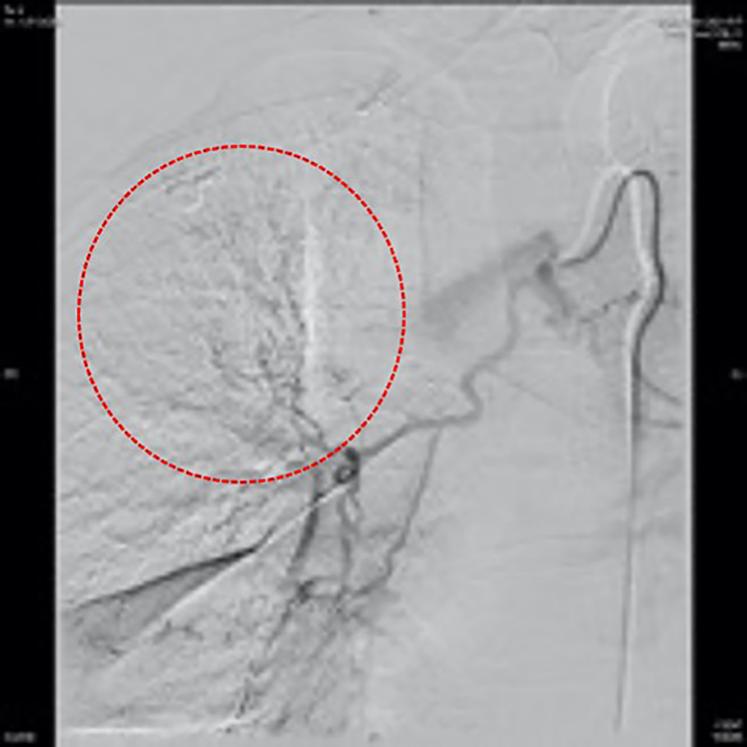

考虑患者存在反复咯血,牟向东主任联合介入科,给予患者行支气管动脉造影及栓塞术,术中可见右侧支气管动脉扩张明显,可见分支扩张。增多及紊乱(图4标注)。给予血管栓塞治疗后咯血停止。

图4. 支气管动脉造影